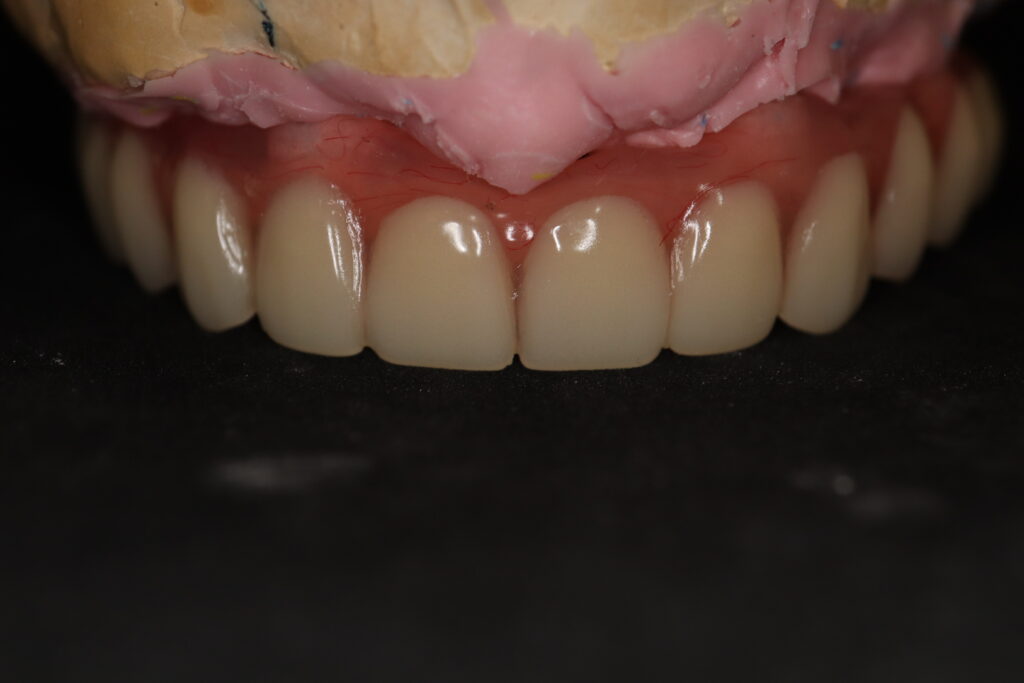

Спустя 7 дней на верхней челюсти зафиксирован металлоакриловый протез из 12 зубов с опорой на 4 дентальные имплантата.

протез